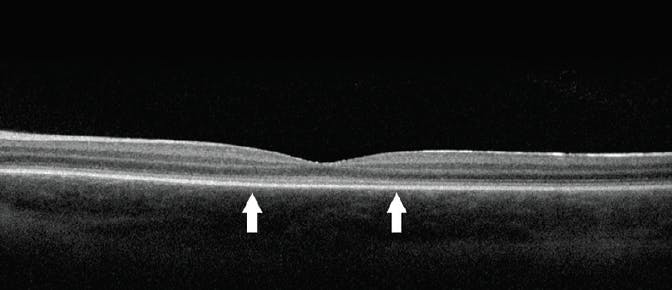

The ID Your IRD program, developed in collaboration with Invitae, also offers free genetic testing for patients with a suspected IRD.2 This test evaluates 293 IRD-associated genes but does not currently include the RPGR gene associated with X-linked retinitis pigmentosa (XLRP, Figure 1). The test offered through ID Your IRD has enrollment, sample collection, and result processes similar to those for My Retina Tracker.

<p>Figure 1. If a patient presents with signs suspicious for XLRP, as seen here, genetic testing may help confirm the diagnosis. The ID Your IRD panel does not include the <em>RPGR</em> gene; consider using the My Retina Tracker program instead.</p>

Figure 1. If a patient presents with signs suspicious for XLRP, as seen here, genetic testing may help confirm the diagnosis. The ID Your IRD panel does not include the RPGR gene; consider using the My Retina Tracker program instead.